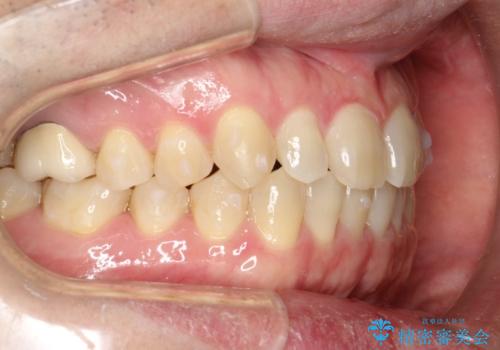

前歯の隙間 インビザラインにて整った歯並びへ

- 前歯の隙間が気になるとのことで来院されました。

インビザラインにて矯正治療を行うこととしました。

下の歯と歯の間にわずかに隙間をつくり、上の前歯の隙間を閉じました。